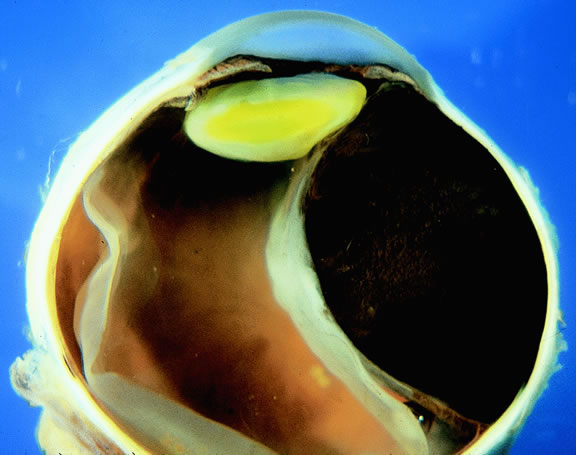

Many choroidal melanomas have a characteristic mushroom or collar button configuration that results when the tumor breaks through Bruch's membrane (Figs. 19, 20, 21, and 22). In such cases there is often secondary choroidal, subretinal, or vitreous hemorrhage. Dilated, intrinsic vessels often are evident in the mushrooming dome of nonpigmented melanomas. The vessels are obscured in more pigmented tumors.48

Fig. 20. Gross photo of mushroom-shaped choroidal melanoma. Amelanotic dome of melanoma anterior to break in Bruch's membrane elevates and detaches retina. Mushrooming head of tumor has a rough papillary surface and contains many vessels.

Choroidal melanomas initially arise in the stroma of the choroid. In early cases, the profile of the sectioned tumor is oval or almond-shaped, and its tissue usually appears relatively cohesive after fixation (Fig. 24). Although some tumors diffusely infiltrate the uvea, most uveal melanomas are relatively well-circumscribed tumors with distinct margins. In many cases the growing melanoma perforates Bruch's membrane and enters the subretinal space where its apex typically assumes a spherical shape that often is likened to a mushroom or collar button (see Figs. 19 to 22.). Dilated vessels often are found in the mushrooming head of the tumor because the ends of Bruch's membrane exert a compressive cinch-like effect on the waist of the tumor (see Fig. 22). Rupture of Bruch's membrane was present in 87.7% of 1527 large- or medium-sized melanomas examined in the COMS.84 Retinal invasion was present in nearly half (49.1%), and tumor cells were found in the vitreous body in one fourth.